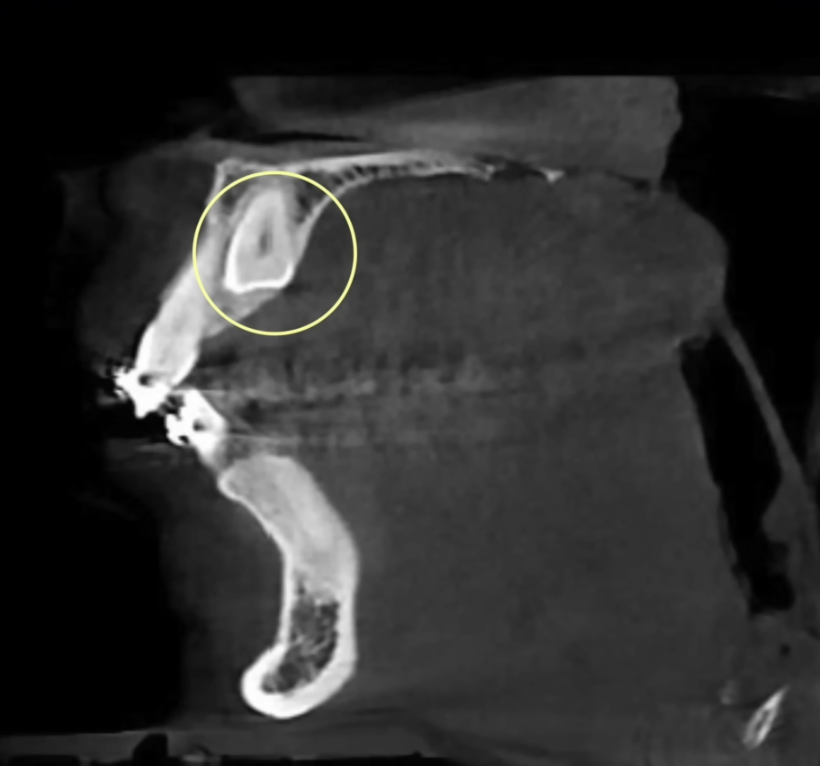

У пациентки не было клыка — он находился глубоко в костной ткани.

КТ клыка

Потому что зуб, находящийся в костной ткани (в данном случае — клык), часто бывает анкилозирован — то есть срастается с костью, и вытащить его просто невозможно.

Также мы попытались достать тот самый клык из костной ткани, но, как и ожидалось — не удалось: клык был анкилозирован, и его пришлось удалить.